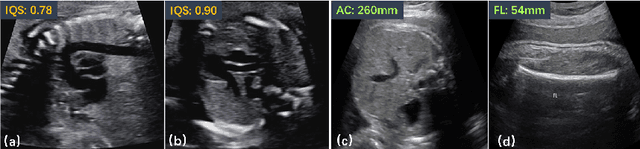

Regression learning is classic and fundamental for medical image analysis. It provides the continuous mapping for many critical applications, like the attribute estimation, object detection, segmentation and non-rigid registration. However, previous studies mainly took the case-wise criteria, like the mean square errors, as the optimization objectives. They ignored the very important population-wise correlation criterion, which is exactly the final evaluation metric in many tasks. In this work, we propose to revisit the classic regression tasks with novel investigations on directly optimizing the fine-grained correlation losses. We mainly explore two complementary correlation indexes as learnable losses: Pearson linear correlation (PLC) and Spearman rank correlation (SRC). The contributions of this paper are two folds. First, for the PLC on global level, we propose a strategy to make it robust against the outliers and regularize the key distribution factors. These efforts significantly stabilize the learning and magnify the efficacy of PLC. Second, for the SRC on local level, we propose a coarse-to-fine scheme to ease the learning of the exact ranking order among samples. Specifically, we convert the learning for the ranking of samples into the learning of similarity relationships among samples. We extensively validate our method on two typical ultrasound image regression tasks, including the image quality assessment and bio-metric measurement. Experiments prove that, with the fine-grained guidance in directly optimizing the correlation, the regression performances are significantly improved. Our proposed correlation losses are general and can be extended to more important applications.